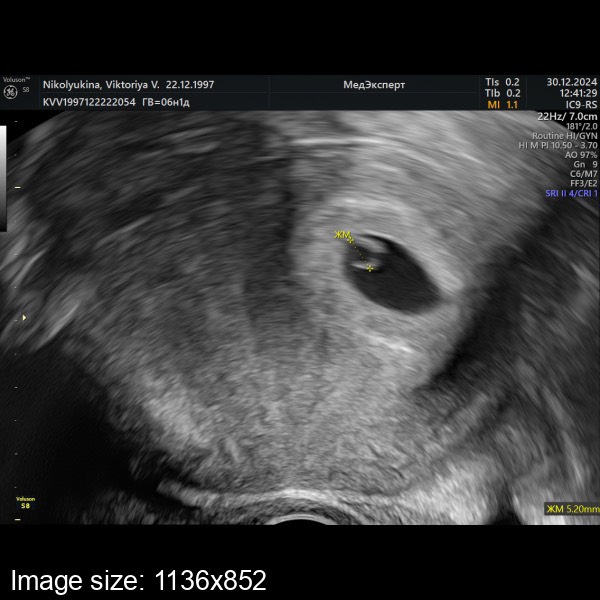

Идем по сроку 🙏🏼 6.1 недель

ПЯ - 18,2 мм

ЖМ - 5,2 мм

КТР - 5,9 мм

ЧСС - 103 ударов/мин

Я видела, как пульсировало сердечко 😍😭

Сказала ни гематом, ни отслоечек, тьфу тьфу тьфу 🙏🏼